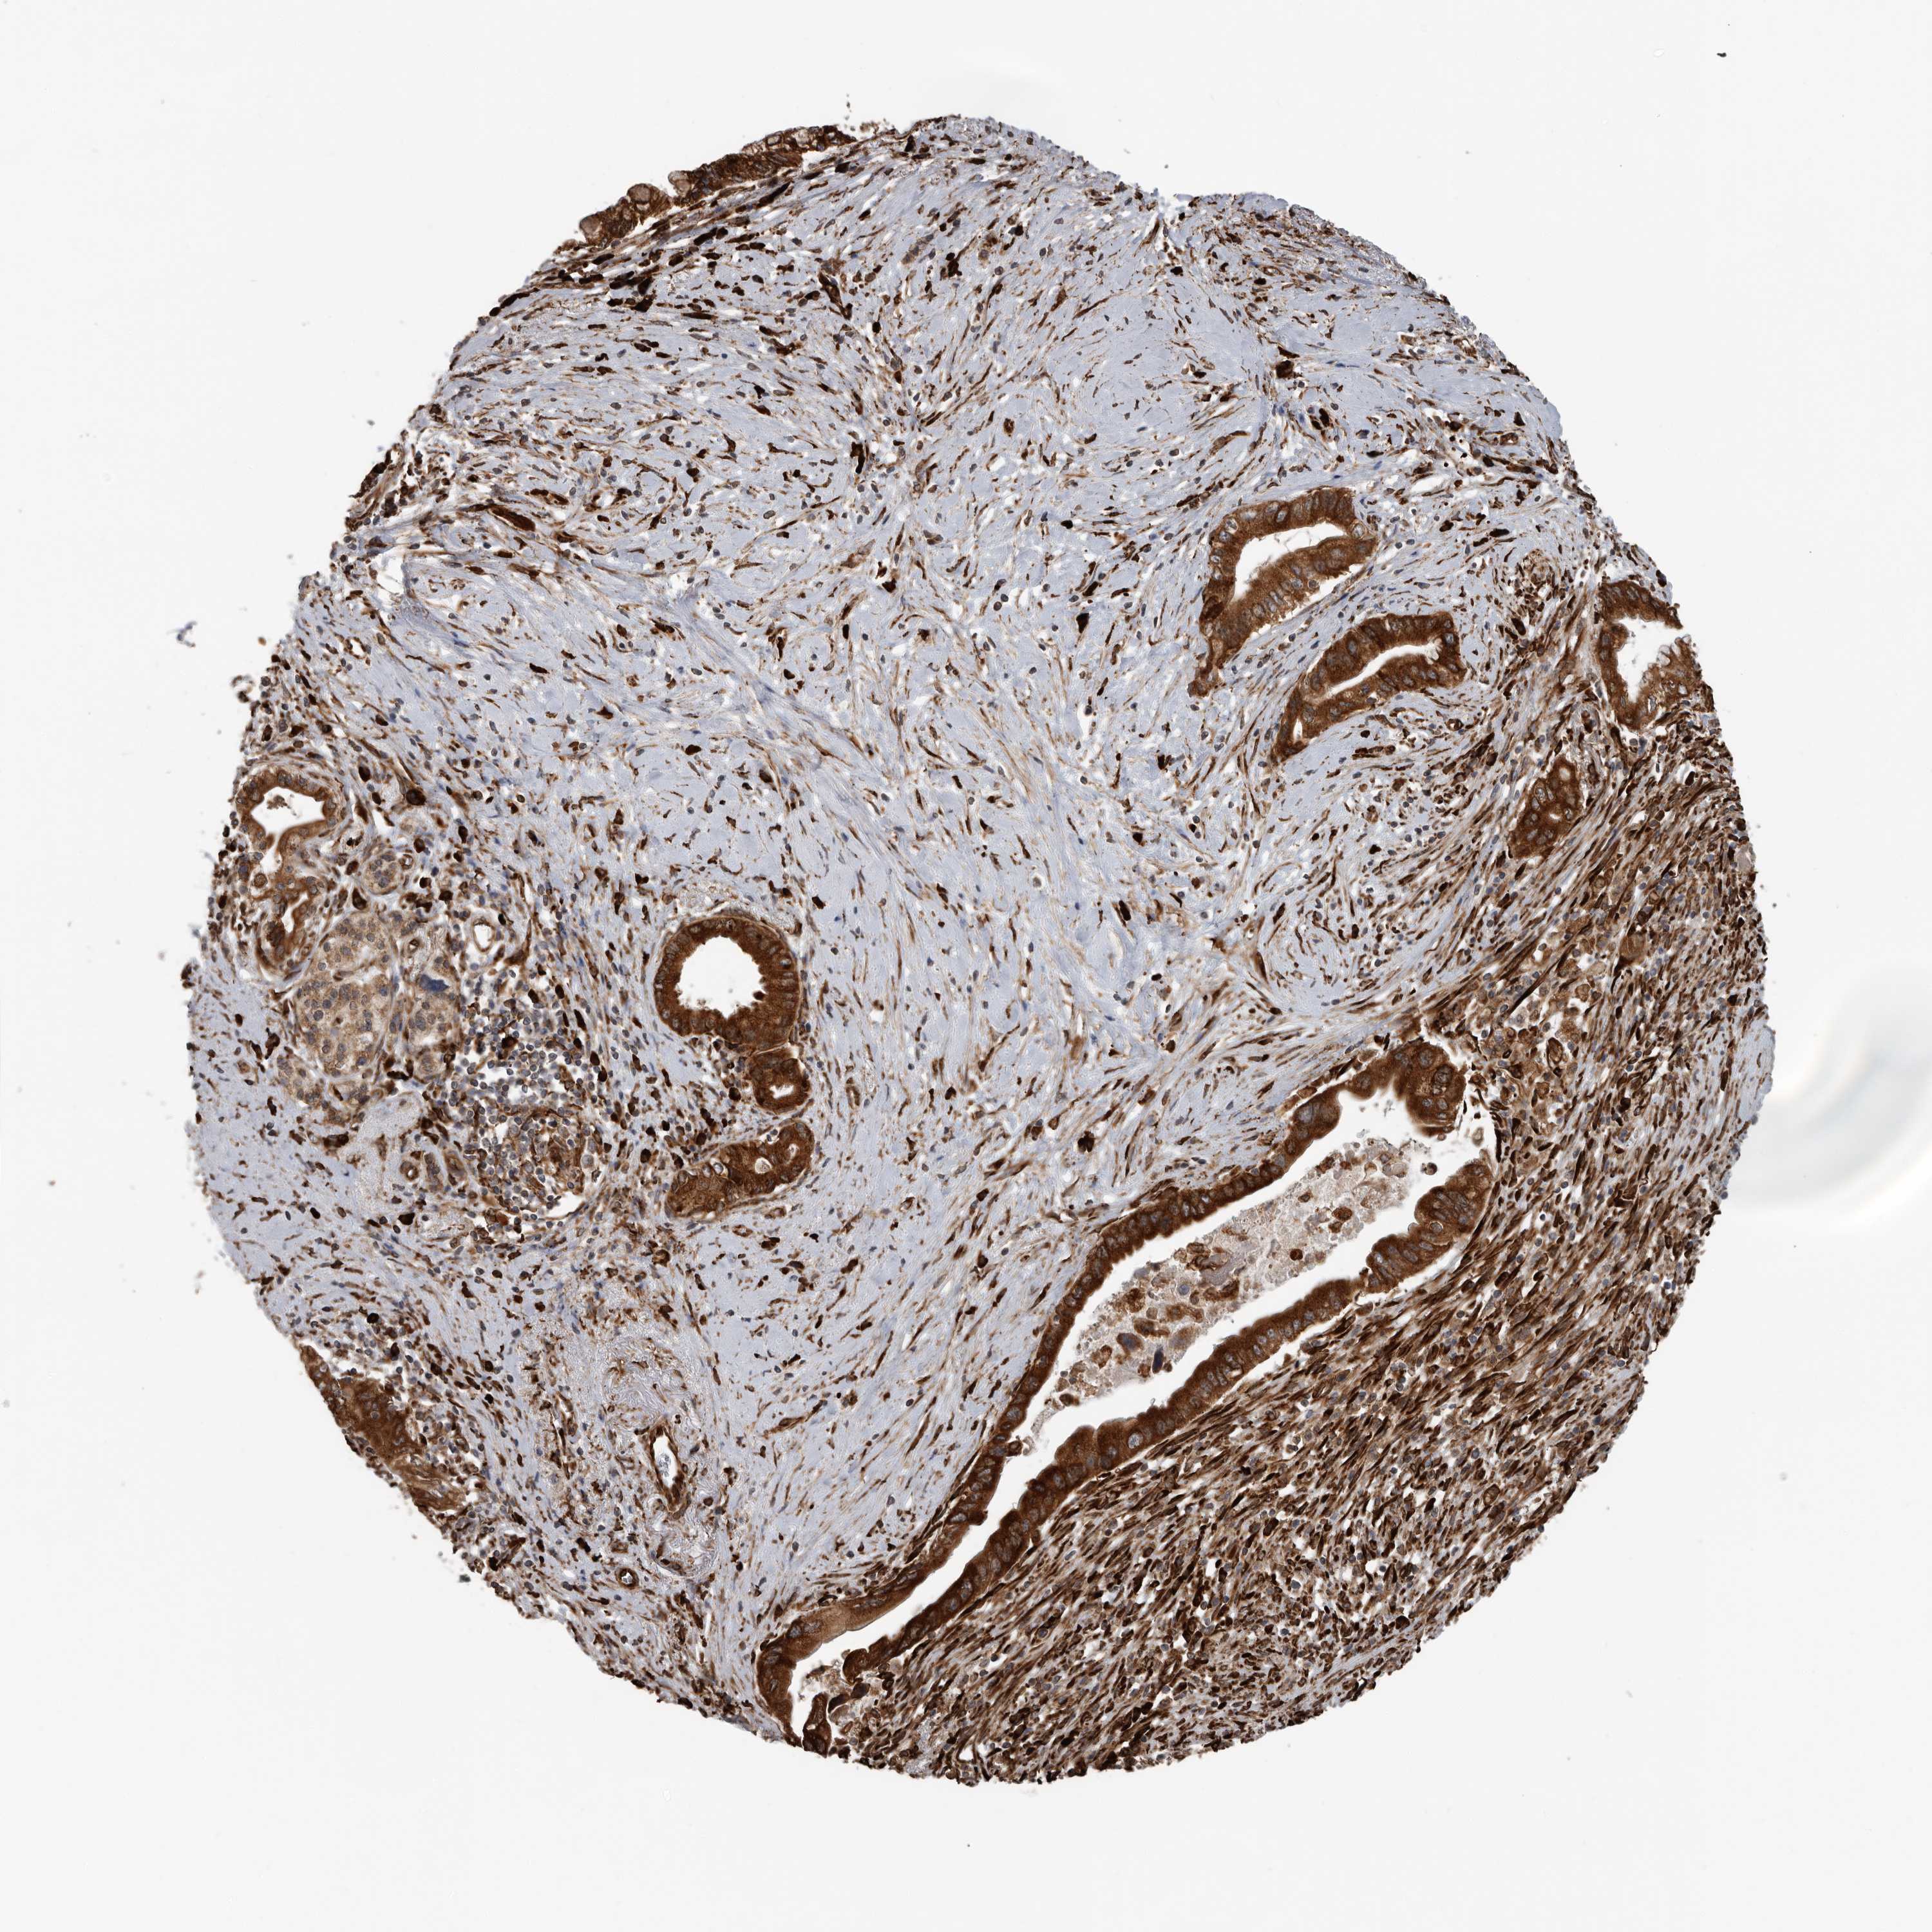

PANCREATIC CANCER - Protein expressioni

A mouse-over function shows sample information and annotation data. Click on an image to view it in a full screen mode. Samples can be filtered based on level of antibody staining by selecting one or several of the following categories: high, medium, low and not detected. The assay and annotation is described here.

Note that samples used for immunohistochemistry by the Human Protein Atlas do not correspond to samples in the TCGA dataset.

Antibody stainingi

Antibody staining in the annotated cell types in the current human tissue is reported as not detected, low, medium, or high, based on conventional immunohistochemistry profiling in selected tissues. This score is based on the combination of the staining intensity and fraction of stained cells.

Each image is clickable and will lead to virtual microscopy that enables deeper exploration of all samples and also displays staining intensity scores, fraction scores and subcellular localization as well as patient and tissue information for each sample.

Antibody HPA028355

Antibody HPA028357

Staining

High

Medium

Low

Not detected

Intensity

Strong

Moderate

Weak

Negative

Quantity

>75%

75%-25%

<25%

None

Location

Nuclear

Cytoplasmic/membranous

Cytoplasmic/membranous,nuclear

Adenocarcinoma, NOS